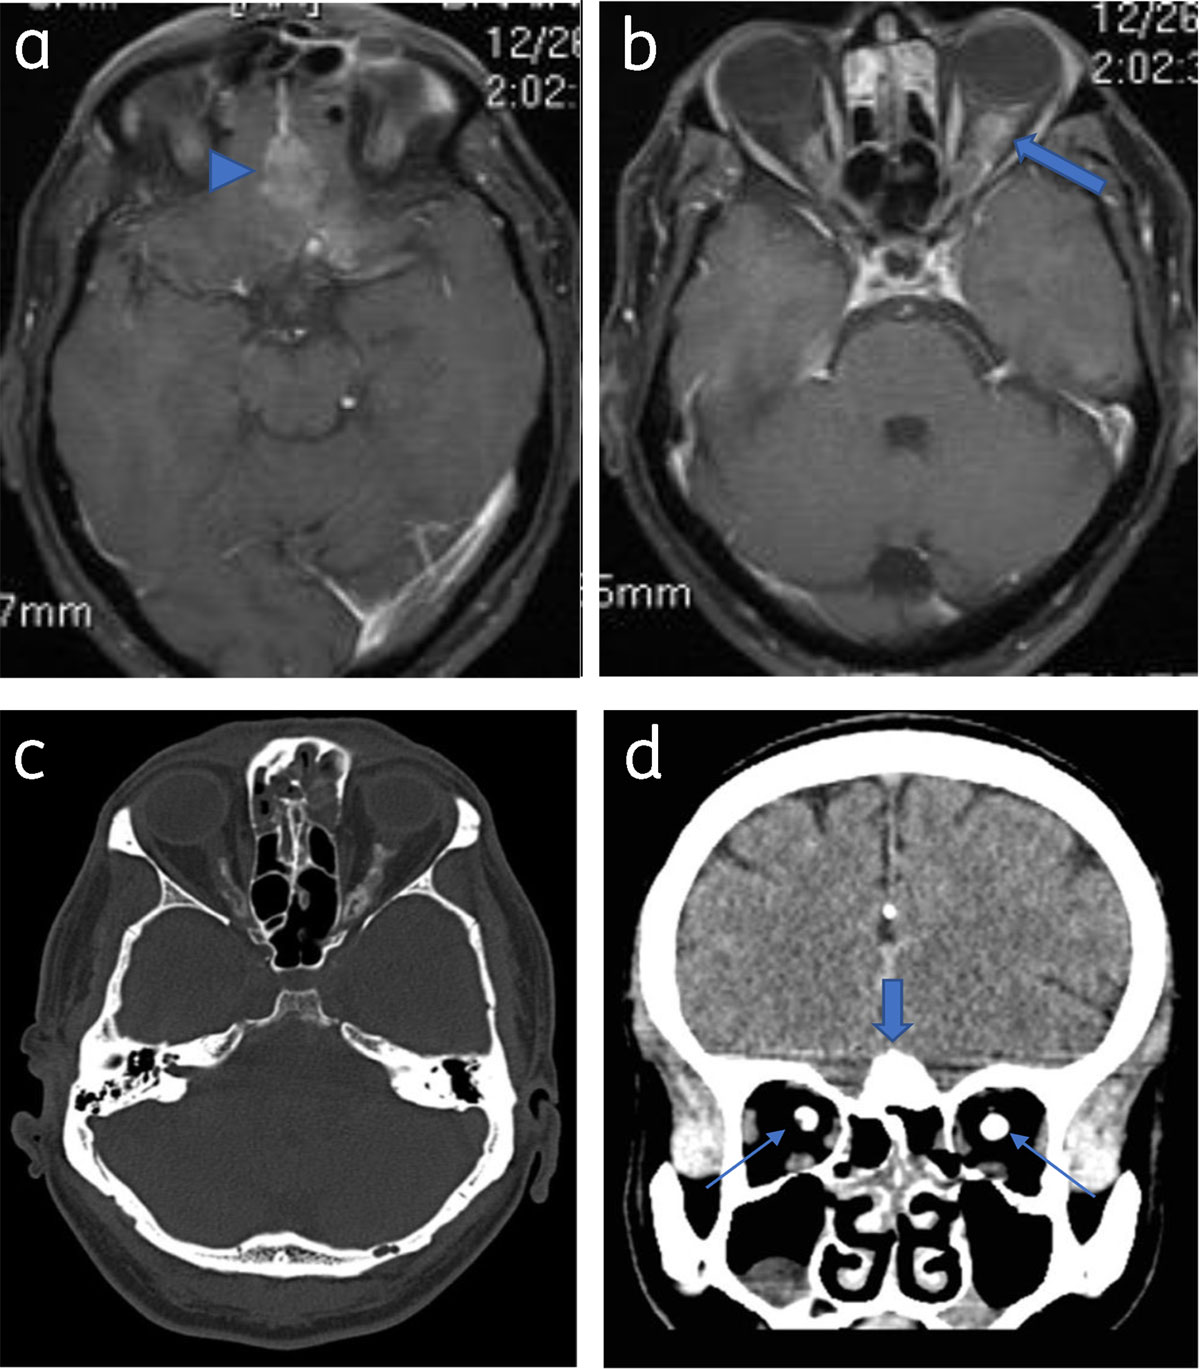

Figure 6

Optic nerve sheath meningioma and olfactory meningioma: Axial post contrast T1WI (a) and (b) shows olfactory grove meningioma (arrowhead) and bilateral optic nerve sheath meningioma (arrow). Axial (c) and coronal NCCT (d) shows calcification in the olfactory groove lesion (thick arrow) and both optic nerves (thin arrows).